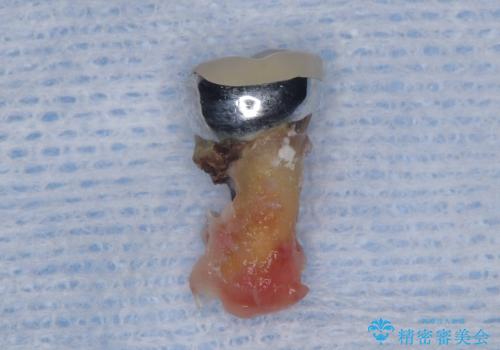

- 過去にヘミセクションが行われていたと思われる左下7番は、大きな歯根嚢胞および根尖病変が認められ、さらに骨縁下カリエスを伴っており、歯肉には瘻孔が形成されている状態でした。

保存は困難と判断し、左下7番は抜歯即時インプラントによる治療を行いました。